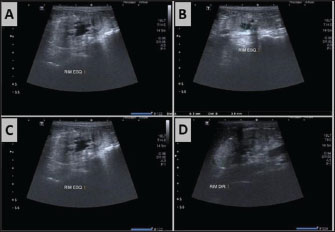

A 3-year-old spayed female Shih-Tzu weighing 3.8 kg was presented to the Veterinary Hospital of the UFLA. The owner reported anorexia and vomiting for the past 2 days, along with polyuria and polydipsia. Physical examination revealed pale mucous membranes, jaundice, halitosis, heart rate of 100 beats per minute (bpm), respiratory rate of 55 respirations per minute (rpm), hyperthermia (39.6°C), and hypotension (80 mmHg). SBP was measured using indirect Doppler sphygmomanometry. The SBP value was determined by averaging five consecutive measurements. The Accu-Chek® device was used to detect hypoglycemia (45 mg/dl). The patient was referred to the intensive care unit, where clinical stabilization was initiated. Biological samples were collected for complete blood count, venous blood gas analysis, and serum biochemistry analyses [alanine aminotransferase (ALT), aspartate aminotransferase, alkaline phosphatase (ALP), gamma-glutamyl transferase, total and fractionated bilirubin, total protein, albumin, globulin, creatinine, urea, phosphorus, chloride, potassium, sodium, and calcium]. Urinalysis, urine culture, blood culture, and antibiotic susceptibility testing were additional diagnostic methods. Urine was obtained via cystocentesis. Abdominal ultrasonography was performed after initial stabilization. Hyperechogenic renal cortex was noted, accompanied by a loss of corticomedullary differentiation and definition in both kidneys. Hypoechoic nodular structures lacking vascularization on Doppler mapping were observed in the left kidney, presumed to be renal abscesses (Fig. 1).

Fig. 1. Ultrasound images of the right and left kidneys on the day of the patient’s admission to the intensive care unit (ICU). (A) Right kidney showing a hyperechoic cortex with loss of corticomedullary distinction and definition. (B, C, D, E and F) Left kidney also displayed a hyperechoic córtex with loss of corticomedullary distinction and definition. Four hypoechoic, nonvascularized nodular structures, the largest measuring 1.04 cm × 0.65 cm, were identified in the cortical region via Doppler mapping. These findings are consistente with the findings of renal abscesses.